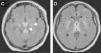

Twenty-three-year old male with a clinical history of biliary pancreatitis one month ago and one cholecystectomy one week ago who now shows clinical manifestations of fever, dizziness, confusion, and significant muscle weakness in lower limbs of two-day duration leading to his admission in the internal medicine unit. The physical examination showed signs of dehydration and postoperative complications were ruled out. Normal brain and abdominal CT scans. The next day, the patient develops drowsiness, quadriplegia, hyporeflexia followed by stupor and hemodynamical instability that leads to the patient's admission to the Intensive Therapy Unit; empirical treatment was started with meropenem and vancomycin. One brain MRI was conducted that confirmed the presence of one hyperintense lesion in the brainstem, fornix, and bilateral thalamus (Figs. 1 A and B, white arrows) without midline shift. The differential diagnosis included vasculitis, herpes, tuberculosis and toxoplasmosis. The biochemical and cytological analysis of the cerebrospinal fluid was nonspecific, and the molecular biology study conducted using the PCR method confirmed the presence of Zika virus ARN. Immunomodulating therapy was initiated with human immunoglobulin (IgG) and five (5) days later a new MRI was conducted that showed the progression of the lesions to cerebral peduncles and basal ganglia (Figs. 2 C and D, white arrows) followed by multiple organ dysfunction and death.